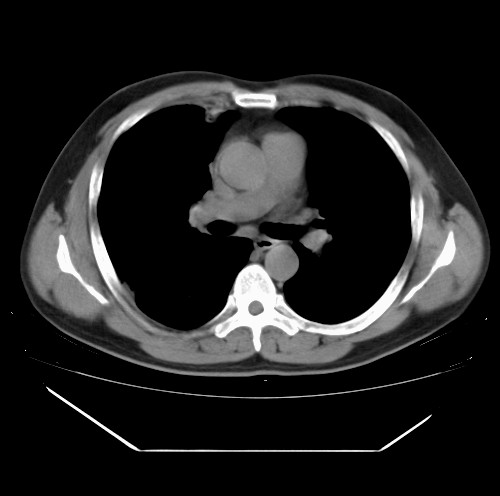

标题: CT22085:双肺多发结节

男,44岁,咳嗽,痰中带血2天。

除肺内及胸膜下可见多发大结节外,在肺小叶中心核、小叶间隔及支气管血管束上亦可见多方小结节,可以认为是随机分布。考虑转移可能性大。

仔细观察病灶形态,病灶边界部分清楚,结合临床症状,首先考虑转移,纵隔内多个肿大淋巴结影。

双肺血管纹理末端多发类圆形结节,边界光滑清晰 气管前腔静脉后淋巴结肿大

考虑转移瘤

沿血管分布,位于血管末端。转移瘤多见,血行性菌栓也可见到。

本例双肺多发类圆形高密度灶,边清,结合病史多考虑双肺多发转移改变,可以结合实验室检查。